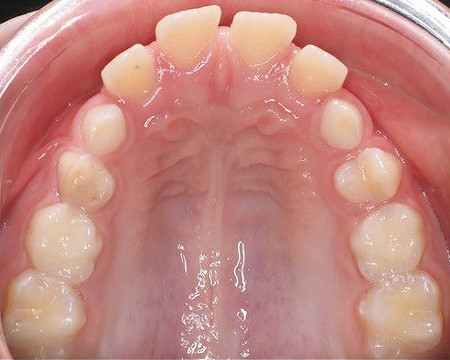

Neunjähriger Patient mit deutlich vergrößertem Overjet aufgrund eines Distalbisses in Kombination mit einer Protrusion der Oberkieferfront. Habits bzw. myofunktionelle Aspekte wurden adressiert. Die Behandlung erfolgte mit einem Invisalign-Schienensatz (56 Aligner) mit Precsion Wings im Rahmen einer Frühbehandlung zur Prophylaxe eines Frontzahntraumas.

Klinisches Fallbeispiel 2 (Abb. 2a–y)

Distalbiss und tiefer Biss bei einem zwölfjährigen Mädchen. Die Behandlung erfolgte mit Invisalign und Precision Wings. Insgesamt waren zwei Schienensätze notwendig. Die Gesamtbehandlung dauerte 18 Monate.Bei der Planung des ClinCheck wurde der tiefe Biss vorwiegend über eine Intrusion der Unterkieferfront behoben, um die Lachlinie der Patientin nicht negativ zu beeinflussen. Die Oberkieferfront wurde nur retrudiert, jedoch vertikal nicht intrudiert. Während der Phase des Mandibular Advancement wurde die Wirkung der Precision Wings durch den Einsatz von Klasse II-Gummizügen unterstützt. Schlussendlich wurde auch der hängenden Okklusionsebene durch eine einseitige Intrusion der Molaren im ersten Quadranten Rechnung getragen.